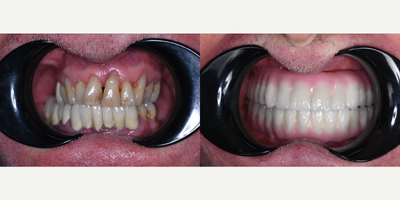

55-64 year old man treated with All-on-4 Dental Implants, Dental Implants

Our patient had severe periodontal disease and all teeth needed to be extracted.Allon4 for upper and conventional 6 dental implants for lower have been performed.